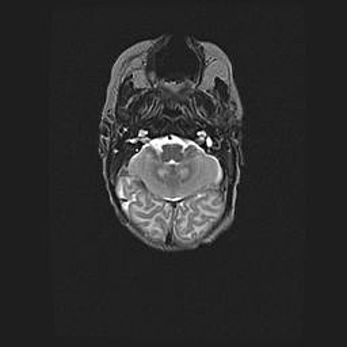

Мальформация Денди-Уокера. Киста задней черепной ямки.

Агенезия мозолистого тела.

Возраст: 2,5 месяца

Вес: 2420 г

Пол: женский

Окружность головы: 37 см

Срок гестации: 32 недели

Мальформация Денди—Уокера — редкий вид патологии ЦНС, представляющий собой врожденный порок развития каудального отдела ствола и червя мозжечка, ведущий к неполному раскрытию срединной (Мажанди) и латеральных (Лушка) апертур IV желудочка мозга. Для этогно синдрома характерна триада симптомов: гипотрофия червя мозжечка и/или полушарий мозжечка, кисты задней черепной ямки, гидроцефалия различной степени. В 70% случаев порок сочетается и с другими аномалиями головного мозга, в частности с агенезией мозолистого тела.